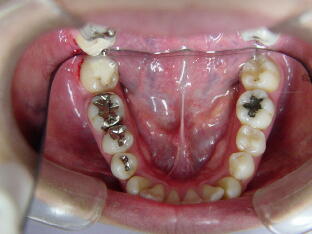

下図の症例写真の歯肉の状態をご覧いただいて、ブラッシングが重要なこ

とは当然ですが、それ以外にもいかに使用する材料によって歯肉に変化が 生じているかについても注目してください。

1.オールセラミックによる審美治療

ジルコニアブリッジ(犬歯から小臼歯)

![]() ![]()